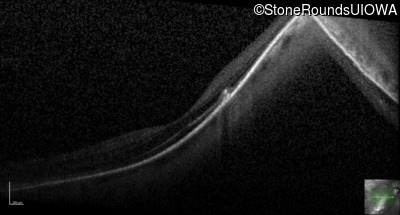

Optical Coherence Tomography - Right - 20/40 +2

Exemplar / OCT Stack